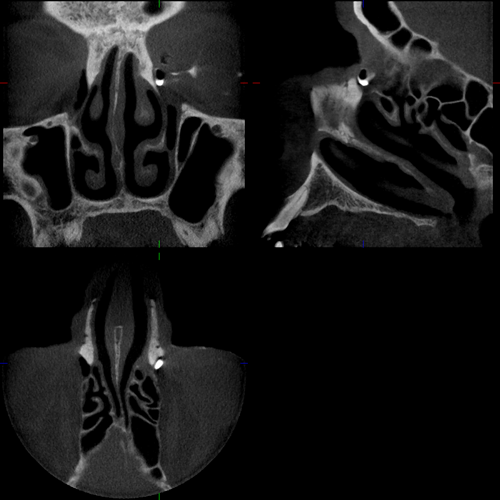

Praesaccale Tränenwegstenose